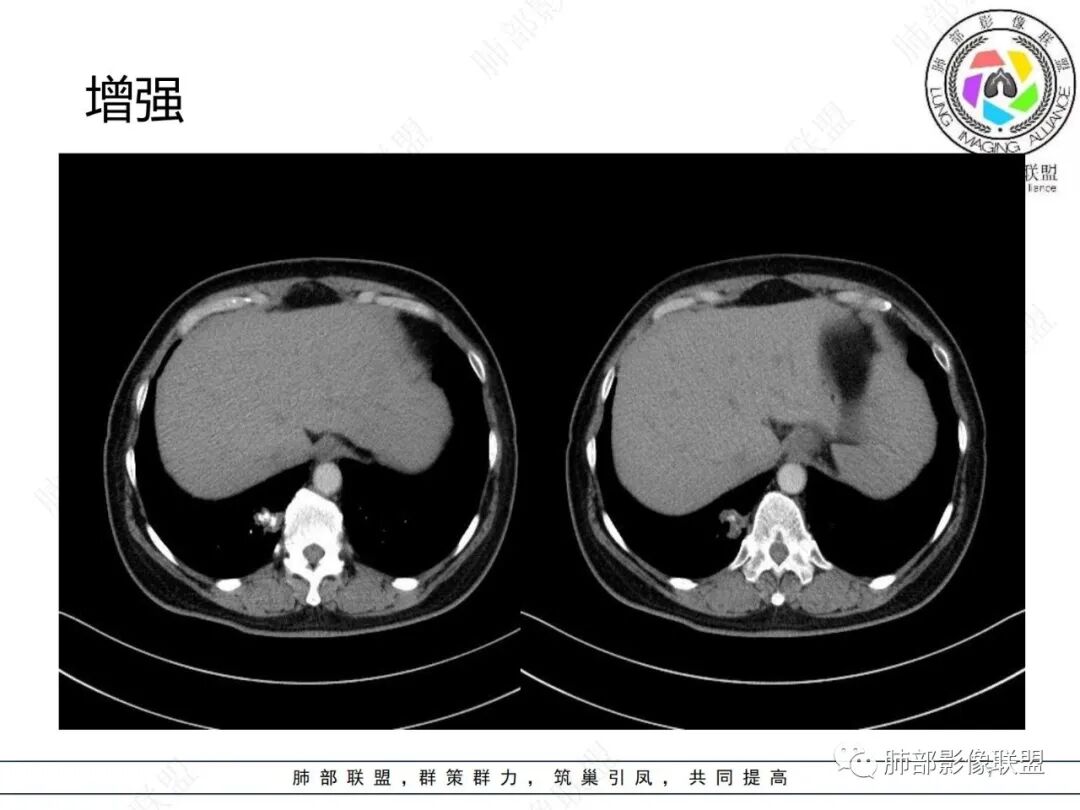

中年女性,右肺下叶后基底段胸膜下不规则稍低密度结节影,内见多发钙化,边缘部分平直,邻近胸膜下脂肪间隙清晰,增强扫描呈均匀轻中度强化,病灶边缘见少许小斑片状影,考虑良性病变,炎性肉芽肿可能,鉴别错构瘤

右肺下叶后基底段结节,形态不规则,有分叶和毛刺,内可见爆米花样钙化,实性成分有强化,绿色无坑肯定考虑错构瘤,晨读估计不会这么简单,所以考虑腺癌?转移性腺癌?鉴别结核

中年女性 右肺下叶不规则实性病灶中心伴钙化,边缘有分叶、胸膜线样牵拉,增强后中等强化,常规思路考虑良性病灶,但是如果有老片 持续观察这个病灶 是否是在增大,腺癌还是可能的,有的肺癌可伴发钙化就是密度没有这么高,疤痕基础上发生也有可能。

CT强化值应该是大于20HU 轻中度强化

右肺下叶胸膜下不规则结节,分叶,其内爆米花样钙化,轻度强化,考虑错构瘤,鉴别腺癌

从强化程度来看,强化不支持错构瘤,病灶有膨胀性有收缩及脐样改变,不能排除肺癌(腺癌)

这个形态还是像腺癌,有膨隆有分叶,边缘磨玻璃边界清,非钙化部分轻度强化。腺癌可以钙化的,估计是干扰项

右肺下叶分叶状实性结节伴钙化,胸膜牵拉似有侵犯,增强后轻度强化,倾向恶性,腺癌可能。

右肺结节,边界清楚,中心钙化,钙化边缘模糊,轻度强化,考虑腺癌,鉴别错构瘤。

右肺下叶内基底段胸膜下分叶状肿块,边界清,密度不均匀,有成簇状钙化(与错构瘤钙化不同),实性部分有强化,肿块边缘凹陷明显(有收缩力),周围集血管束特点,方向首选肺肿瘤,考虑肺腺Ca。